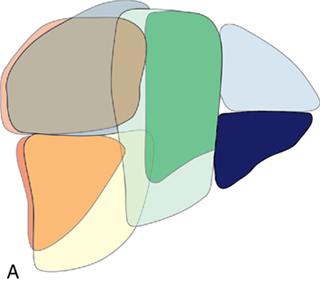

Ritu K. Kashikar, Shrinivas B. Desai Imaging is the mainstay of noninvasive diagnosis of the spectrum of abdominal pathologies or proving absence off thereof. Knowledge of normal anatomy and important normal variants is thus essential for the radiologist in order to avoid misinterpretation or erroneous diagnosis. This chapter highlights the normal anatomy of the hepatobiliary systems including the blood vessel and draining ducts and discusses relevant anatomical variants which may have important clinic implications. The liver is the largest abdominal organ, occupying the right upper abdominal quadrant and is in close approximation with the diaphragm, stomach and the gallbladder. It is largely covered by the costal cartilages. The liver is encapsulated by Glisson’s capsule which is a dense layer of connective tissue. It is covered by peritoneum, except in the regions of gallbladder fossa, fossa for inferior vena cava (IVC), and the bare area. The bare area is the posterocranial aspect of the liver, adjacent to the dorsal body wall, which is not covered by peritoneum. The liver has two surfaces, the convex diaphragmatic surface and a concave visceral surface. The slit in the hepatic hilum is called the porta hepatis and is penetrated by the right and left hepatic ducts (LHDs), hepatic artery and portal vein (PV). The distal portion of the lesser omentum is called the hepatoduodenal ligament and contains the common bile duct (CBD), hepatic artery, PV, nerves of liver and lymphatics. The liver has dual blood supply with hepatic artery providing 25% of hepatic blood and rest by portal vein (Fig. 9.2.1). Five ligaments connect the liver to the undersurface of the diaphragm. These include the falciform, the coronary and two lateral ligaments, all of which are peritoneal folds. The fifth ligament is a fibrous cord-like structure and represents the obliterated umbilical vein. The peritoneum invaginates into the liver parenchyma leading to formation of fissures. There are four normal fissures: fissures for the ligamentum teres, ligamentum venosum and gallbladder and the transverse fissure (Fig. 9.2.2). The liver is organized into microscopic functional units called lobules or acini. A central terminal hepatic venule surrounded by four to six terminal portal triads form a polygonal unit called the hepatic lobule. The terminal portal triad branches line the periphery of the unit. Between the terminal portal triads and the central hepatic venule the hepatocytes are arranged in one cell thick plates, surrounded by sinusoids. The blood flows from the terminal portal triad through sinusoids into terminal hepatic venule. Bile formed within the hepatocytes empties into terminal canaliculi which coalesce into the bile ducts (Fig. 9.2.3). This structure of the functional hepatic unit forms the basis of various functions of the liver. The normal relations of the liver are: The liver can be divided into right, left and caudate lobes. The right and left lobes are separated by the interlobular fissure and is oriented along a line passing through the gallbladder fossa inferiorly and the middle hepatic vein (MHV) superiorly (Fig. 9.2.4). This plane runs from the left of the IVC to the left of the gallbladder fossa and is a called the Cantlie’s line. Use of standardized, segmental anatomy is imperative because it facilitates communication and treatment planning. The segmental anatomy of liver is primarily based on vascular anatomy. The right lobe is divided into anterior and posterior sectors by of the right hepatic vein (RHV). The left lobe is divided into medial and lateraI sectors by an oblique plane connecting the left hepatic vein (LHV) and the falciform ligament. The liver is divided into upper and lower segments at the level of main portal vein (MPV) bifurcation (Fig. 9.2.5). Various systems are used in classification of liver anatomy. These are discussed in Table 9.2.1. The Couinaud’s system is the most commonly used and divides eight sections/segments which are discussed in details below (Table 9.2.2). 1. Segment 1 – Caudate lobe Bounded anteriorly and medially by the fissure for ligamentum venosum (Fig. 9.2.6). 2. Segment 2: Superior segment of the left lateral sector/section Bounded medially by falciform ligament and inferiorly by plane of MPV, also known as the posterior lateral sector (Bismuth, FCAT) (Fig. 9.2.7). 3. Segment 3: Inferior segment of left lateral sector/section Bounded medially by the falciform ligament and superiorly by the plane of the MPV bifurcation, also referred to as lateral anterior sector (Bismuth, FCAT) (Fig. 9.2.8). 4. Segment 4: Left medial sector/section Bounded laterally by falciform ligament and medially by Cantlie’s line (Fig. 9.2.9). 5. Segment 5: Inferior segment of the right anterior sector/section Bounded anteriorly by the gallbladder fossa and posteriorly by the plane of the RHV, superiorly bounded by the plane of MPV bifurcation (Fig. 9.2.10). 6. Segment 6: Inferior segment of the right posterior sector/section Bounded anteriorly by plane of the RHP and superiorly by the plane of the MPV bifurcation (Fig. 9.2.11). 7. Segment 7: Superior segment of the right posterior sector/section Bounded anteriorly by the plane of the RHV and inferiorly by the plane of the MPV bifurcation (Fig. 9.2.12). 8. Segment 8: Superior segment of the right anterior sector/section Bounded anteriorly by the plane of the gallbladder fossa and MHV, posteriorly bounded by the plane of the RHV and inferiorly by the plane of the MPV bifurcation (Fig. 9.2.13). Owing to its broad area of contact with the anterior abdominal wall, the liver is an ideal organ for evaluation with sonography. Ultrasound is commonly used for evaluation of size of the liver. On longitudinal scans obtained through the midhepatic line, if the liver measures 13 cm or less, it is normal in 93% of individuals (Fig. 9.2.14). The size of liver in various planes is discussed in chapter on normograms. When the area of contact between the liver and the anterior border of the right kidney, exceeds below two thirds of the kidney, the liver is considered as enlarged. The normal liver is homogeneous with fine echoes and appears evenly bright. The hepatic veins, PV and fissures interrupt the homogeneity of the liver parenchyma (Fig. 9.2.15). The parenchymal echogenicity may vary depending on the equipment, transducer and gain settings and should be judged by comparison with internal references like right renal cortex, body of the pancreas and PV walls. When compared with the adjacent normal right renal cortex the liver normally appears hyperechoic or isoechoic. The pancreas in a young individual is hypoechoic compared to the liver, and isoechoic in middle aged adults. As age progresses and fatty infiltration of the pancreas occurs, the pancreas appears hyperechoic to the liver. The liver is hypoechoic to the spleen. The normal liver reveals a density of 55–65 HU on nonenhanced scan and should appear homogenous with the exception of hypodensity in the regions of vessels and fissures. The liver parenchymal enhancement is minimal the arterial phase, with increase in density by only approximately 10 HU. This phase is usually to access vascular anatomy and to detect neovascular enhancing lesion like HCC, metastasis. Considering the fact that 75% of heptic venous supply is from the PV, the normal hepatic parenchyma shows maximum enhancement in the portal venous phase. During the venous/delayed phase the hepatic attenuation starts falling (Fig. 9.2.16). The hepatic fissures appear as linear fat containing structures. All the four fissures are well identifies on CT (Figs. 9.2.17–9.2.20). Normal liver should demonstrate uniform T1 signal similar or isointense to the paraspinal muscles and slightly hyper intense to the spleen. No signal drop should be seen on in or opposite phase. On T2W1 images liver appears slightly hyperintense to paraspinal muscles, isointense to pancreas and hypointense to spleen (Fig. 9.2.21). Following administration of extracellular contrast agents the normal liver parenchyma enhances on PV phase similar to that seen on CT. The arterial phase is preserved to determining vascular anatomy, variants and tumoural enhancement. Gadoxetic acid (Eovist) and gadobenate dimeglumine (MultiHance) are hepatobiliary agents showing excretion by the liver. In the case of gadoxetic acid, hepatic excretion is ~50%, which allows imaging in the hepatobiliary phase at ~20 minutes following injection. Gadobenate has only 3%–5% biliary excretion with hepatobiliary phase at approximately 40 minutes (Fig. 9.2.22). This property makes these agents useful in detection of nonhepatocyte containing lesions which appear hypointense to background liver on hepatobiliary phase. Hepatic anatomic variants are relatively common and represent normal interindividual variation of liver morphology. Normal Anatomic Variants Anatomic anomalies Accessory and pseudofissures may be seen in the liver. True accessory fissures result from infolding of the peritoneum usually along the undersurface of the liver and are rare. The inferior accessory fissure is the commonest accessory fissure and divides the posterior segment of the right hepatic lobe into lateral and medial portions. Diaphragmatic slips may cause indentation over the liver surface and are not commonly seen on imaging (Fig. 9.2.23). Leftward extension of the lateral segment of the left hepatic lobe appearing as a crescentic density that wraps around the spleen is referred to as sliver of liver. The left lobe of the liver may exhibit various forms: leaf like; spatular; truncated pyramid/wedge shaped; and a bifid appearance (Fig. 9.2.24). Elongated left lobe may be mimic splenomegaly, perisplenic hypoechoic collections or less commonly tumours. Imaging clues to diagnosis are establishing contiguity with liver and visualization of parenchymal vessels coursing through. The portion of the liver that extends medially from the right lobe between the IVC and fissure for ligamentum venosum is called the caudate lobe. The caudate lobe is divided inferiorly into a lateral caudate process and a medial papillary process. The medial papillary process projects medially towards the pancreatic head and has applied importance (Fig. 9.2.25). Riedel’s lobe is a tongue-like projection from the anterior aspect of the right lobe and the most common accessory lobe of the liver. It is seen most frequently in asthenic women. The reported prevalence of RL, ranges from 3.3% to 14.5% and the prevalence is higher in women than in men. It can be 20 cm or more in length and may extend up to the iliac fossa. It is usually asymptomatic and is discovered incidentally (Fig. 9.2.26). Accessory liver lobes are defined as a supernumerary lobe of normal hepatic parenchyma in continuity with the liver. This is a rare entity and usually occurs as a result of congenital ectopic hepatic tissue, although rarely may occur as a result of trauma or surgery. Various systems are proposed for classification of ALL. Another method of classification has been proposed based on biliary drainage and presence or absence of capsule. Accessory lobes can be readily diagnosed and characterized on CT or magnetic resonance imaging (MRI) done for related or unrelated conditions. CT shows the lesion as a soft–tissue density mass attached to the liver and isodense to the organ. The portal/hepatic venous branches can be seen coursing through it, in contiguity with the liver (Fig. 9.2.27). The coeliac axis trifurcates into common hepatic, splenic and left gastric arteries at the level of T12–L1. The common hepatic artery becomes the proper hepatic artery after origin of the gastro-duodenal artery. The hepatic artery proper ascends anterior to the PV and medial to the CBD and divides in to right and left hepatic artery (LHA). Occasionally the middle hepatic (segment 4) artery arises from hepatic artery proper. The hepatic artery appears as a tubular hypoechoic structure and shows antegrade flow on Doppler (Fig. 9.2.28). Normally the resistive index is low ranging between 0.55 and 0.7. The hepatic artery, its anatomy, branches, course, calibre are best evaluated on arterial phase of dynamic CT (Fig. 9.2.29). This is also the preferred modality prior to hepatobiliary surgical planning. Contrast-enhanced MRI also shows the above details but spatial resolution is lower. Road map of the arterial vascularity of the donor and recipient is a prerequisite for transplant surgery and complex hepatobiliary surgery. Detailed hepatic arterial anatomy and its variations have its significance in liver surgeries and interventional hepatic procedures, relative to the hepatic lobe involved. A classification method was described by Michel et al. in 1955, and is discussed in Table 9.2.3 (Fig. 9.2.30). I: standard anatomy ~60% (range 55%–61%) II: replaced LHA ∼7.5% (range 3%–10%) III: replaced RHA ~10% (range 8%–11 %) IV: replaced RHA and LHA ~1% V: accessory LHA from LGA ~10% (range 8%–11%) VI: accessory RHA from SMA ~5% (range 1.5%–7%) VII: accessory RHA and LHA ~1% VIII: accessory RHA and LHA and replaced LHA or RHA ~2.5% IX: CHA replaced to SMA ~3% (range 2%–4.5%) X: CHA replaced to LGA ~0.5% Other unclassified variants are: The two most common variants are the replaced right hepatic artery (RHA) arising from the SMA (Fig. 9.2.31) and replaced LHA arising from the left gastric artery (Figs. 9.2.32–9.2.34). Segment 4 artery – Middle hepatic artery (MHA) The middle hepatic artery usually arises from the LHA, it may, however, arise from the RHA (Fig. 9.2.35). The knowledge regarding origin of MHA is imperative in transplant surgery. The MHA can arise from RHA in Patients with replaced LHA. In patients with replaced RHA, the MHA arises from LHA (Fig. 9.2.36). Because of the considerable variability of hepatic arterial anatomy, assessment of this anatomy is crucial in the preoperative evaluation of potential living liver donors. Relevance of donor and recipient arterial anatomy is discussed in details in chapter on liver transplant. The relationship between the arterial variant and tumour is important to establish prior to major surgeries. Injuries to aberrant hepatic vessels and secondary ischaemic biliary strictures can be avoided. A replaced RHA has a more posterior course and long length. This variant may be advantageous in patients undergoing right lobar resection. However, there is greater propensity of involvement of replaced RHA by pancreatic head. The radiologist must be vigilant in reporting this variant (Fig. 9.2.37). Accessory RHA can, however, be sacrificed even if encased by neoplasm. An accessory LHA needs to be ligated separately in surgeries where blood supply in the porta hepatis is occluded. Replaced LHA from LGA maybe injured in case of surgeries at the level of hiatus. Hence this variant should be informed to surgeon in patients undergoing gastric surgeries. Preoperative mapping of the hepatic arterial anatomy prior to placement of intraarterial chemotherapy pumps is essential because it helps in deciding whether the candidate is suitable for the procedure and also if technical modifications are needed. The intraarterial infusion pump should be placed in the dominant hepatic artery as proximal as possible, but beyond GDA origin. Inpatients with standard anatomy, the pump is usually placed in the hepatic artery prior just after GDA origin. The location of pump can be modified in patients with variant anatomy, based on origin of GDA and dominant hepatic vessel. The PV is the main vessel in the portal venous system and drains blood from the gastrointestinal tract and spleen to the liver.